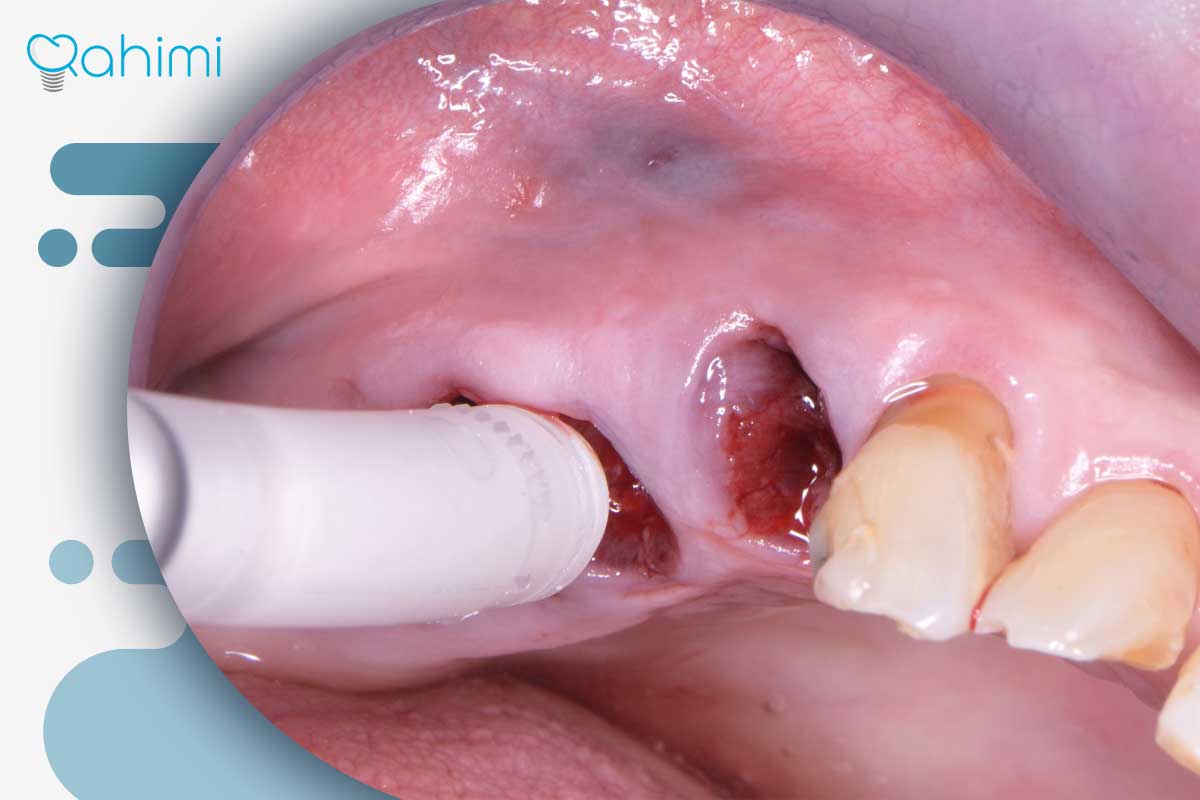

- بررسی دقیق محل زخم :متخصص، محل زخم و وضعیت بخیهها را بررسی و عوامل تحریککننده را حذف میکند.

- پاکسازی حرفهای :در صورت وجود التهاب، از ابزارهای مخصوص تیتانیومی و دستگاه ایرپولیش استفاده میشود تا بافتها بدون آسیب تمیز شوند.